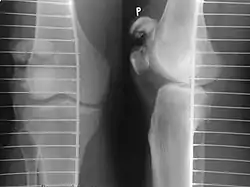

Comminuted fracture of patella